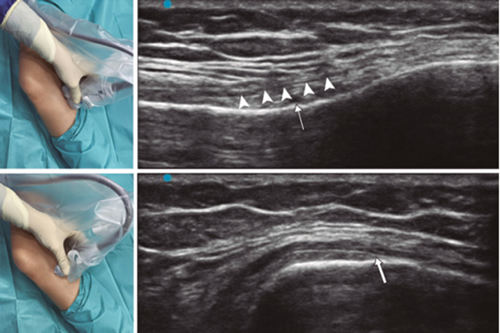

Ultrasound-guided genicular nerve radiofrequency

Fig. 3. Sonoanatomy and technique for performing superior medial genicular nerve block (SMGN). The transducer is located on the distal long axis of the femur and once the position of the SMGN (asterisks) is known, the probe is rotated 90 degrees to obtain a view of the femur short-axis (don't forget to keep the same depth that we find the SMGN on the long axis). VM (vastus medialis).

In order to achieve a correct location of anatomical landmarks by ultrasound we must place the patient in supine position with the knee flexed and a pillow under the popliteal fossa (14,16,19).

Fig. 4. Sonoanatomy and technique for performing inferior medial genicular nerve block (IMGN). The transducer is located on the proximal long axis of the tibia and we identify the vasculonervious package of the IMGN (arrow) just below medial collateral ligament (arrowheads). Then the probe is rotated 90 degrees to obtain a short-axis view of the tibia (don't forget to keep the same depth as the IMGN found on the long axis).

After performing knee asepsis/antisepsis, surgical field placement, and the sterile sheath of the high frequency linear transducer, we proceed to locate the SMGN (Figure 3). Placing the probe in a coronal plane on the inner face of the knee, we slide it cranially to visualize the junction of the metaphysis to the femoral diaphysis and the superior medial genicular artery/nerve (ASMGN), usually located near the periostium of the femur (if this neurovascular structure is not found, the junction between metaphysis and femoral diaphysis is taken as a reference). The mid-point of the transducer corresponding to ASMGN is then marked on the skin and the transducer is rotated to be placed in the transverse or axial plane to view ASMGN on the short axis (if this structure is not visible, confirm that we are at 50 % depth of the femur). In this cross-section the needle of the TRF is advanced in plane from anterior to posterior toward the ASMGN or to a depth of 50 % of the thickness of the femur. Finally, the transducer is rotated 90° again, leaving it in a coronal plane to check that the needle tip is near the ASMGN or the junction of the metaphysis and femoral diaphysis (14,16,19).

To locate the IMGN (Figure 4), we placed the transducer in a coronal plane on the inner face of the knee, sliding it caudally to identify the diaphysis junction with the tibial metaphysis and the inferomedial genicular artery/nerve (AIMGN). And we repeat the same steps we used for SMGN. If the AIMGN is not found, the reference to be taken shall be the depth of 50 % of the thickness of the tibia (14,16,19).

To locate the SLGN, the patient must be supine with the lower limb in internal rotation, obtaining good exposure to the lateral side of the thigh. We place the linear transducer in a coronal plane on the lateral side of the knee, slide it in a cranial direction to visualize the junction of the metaphysis with the femoral diaphysis and the superior lateral genicular artery/nerve (ASLGN), and repeat the same steps that we use for SMGN (14,16,19).

Then we found that the threshold of sensory stimulation at 50 Hz that triggers a paresthesia or pain is less than 0.6 V, and to avoid motor nerve damage there should be no fasciculations of the lower limb with a motor stimulus at 2 Hz with 2.0 V. If everything is correct, we administered 2 ml of lidocaine 2 % or mepivacaine 2 % in each nerve and performed the TRF at 80 °C for 90 seconds (9,14).

In our review we find other anatomical landmarks that can help us locate the genicular nerves. Yasar et al. (20) identified that the SMGN is located one centimeter before the adductor tubercle, the IMGN is located at the midpoint between the peak of the medial tibial epicondyle and the beginning of the insertion of the medial collateral ligament fibers over the tibia.